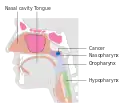

Nasopharyngeal carcinoma (NPC), or nasopharynx cancer, is the most common cancer originating in the nasopharynx, most commonly in the postero-lateral nasopharynx or pharyngeal recess (fossa of Rosenmüller), accounting for 50% of cases. NPC occurs in children and adults. NPC differs significantly from other cancers of the head and neck in its occurrence, causes, clinical behavior, and treatment. It is vastly more common in certain regions of East Asia and Africa than elsewhere, with viral, dietary and genetic factors implicated in its causation.[1] It is most common in males. It is a squamous cell carcinoma of an undifferentiated type. Squamous epithelial cells are a flat type of cell found in the skin and the membranes that line some body cavities. Differentiation means how different the cancer cells are from normal cells. Undifferentiated cells are cells that do not have their mature features or functions

Nasopharyngeal carcinoma, also known as nasopharyngeal cancer, is classified as a malignant neoplasm, or cancer, arising from the mucosal epithelium of the nasopharynx, most often within the lateral nasopharyngeal recess or fossa of Rosenmüller (a recess behind the entrance of the eustachian tube opening). The World Health Organization classifies nasopharyngeal carcinoma in three types, in order of frequency: Non-keratinizing squamous cell carcinoma; keratinizing squamous cell carcinoma; and basaloid squamous cell carcinoma.[14] The tumor must show evidence of squamous differentiation, with the non-keratinizing type (also known as lymphoepithelioma) the tumor most strongly associated with Epstein-Barr virus infection of the cancerous cells.[15]